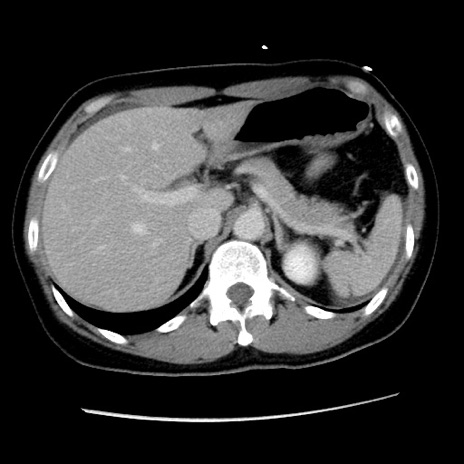

症例10(横断像)

【症例】 50歳代女性

【主訴】 腹痛

【現病歴】前日生レバーを食べた。今朝に排便あり。 昼前に突然発症の腹痛を生じ、当院救急外来を受診した。

【既往歴】 子宮筋腫にてで子宮全摘後

【身体所見】 意識清明、腹部:平坦、軟、下腹部やや左を中心に圧痛・反跳痛あり、筋性防御あり

【データ】WBC 7800、CRP 0.07